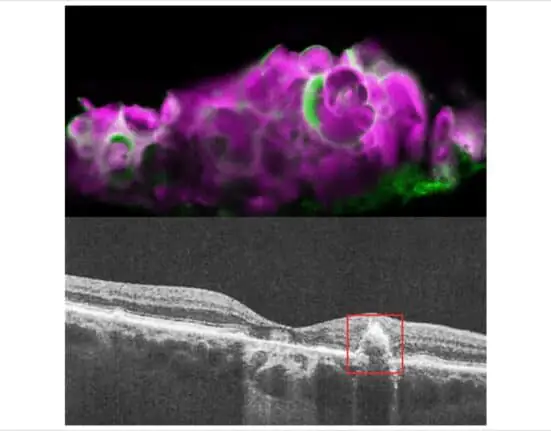

Researchers recently found the calcium-containing mineral hydroxyapatite (HAP) in dry AMD deposits. HAP is a key component of tooth enamel and bone. Small balls of HAP filled with cholesterol called spherules were found only in drusen from people with dry AMD and not in those with wet AMD or without AMD.

The NEI’s researchers found that if they starved RPE cells grown in transwells, a type of cell culture system, for nine days, the cells began to deposit HAP. The researchers determined that amelotin, encoded by the gene AMTN, is strongly upregulated after extended starvation and is responsible for the mineralization of HAP in their cell culture model. Blocking this pathway in their RPE cell line also blocked the production of these drusen-like deposits.

To verify that their cell culture model was accurately representing dry AMD, the researchers examined human cadaver eyes with dry AMD, wet AMD, or without AMD. They found HAP and amelotin only in the eyes with dry AMD and not in the other eyes. While amelotin was found sometimes in areas of dry AMD and without drusen, it was primarily present in soft drusen areas with large deposits of HAP.